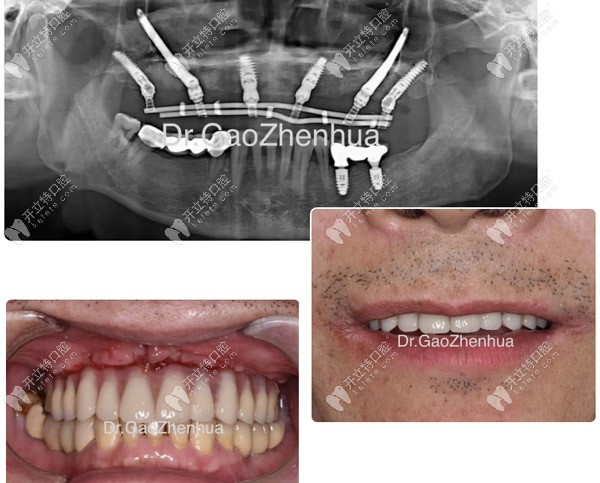

顴種植位點(diǎn)不得已還是放在貫通位點(diǎn),竇底適當(dāng)植骨,前牙區(qū)靠鼻底硬骨板雙皮質(zhì)固位獲得穩(wěn)定性,經(jīng)過2個(gè)小時(shí)的手術(shù),實(shí)現(xiàn)了即刻負(fù)重的預(yù)期!

當(dāng)天做完VIIV穿顴穿翼手術(shù)

當(dāng)天做完VIIV穿顴穿翼手術(shù)▲

鼎植口腔的VIIV穿顴穿翼是一項(xiàng)針對(duì)口腔缺骨顧客實(shí)現(xiàn)即刻種植、即刻完成固定牙修復(fù)的技術(shù)。

即便是重度牙槽骨萎縮、骨質(zhì)疏松、糖尿病及高齡人群也可以通過穿顴穿翼技術(shù)實(shí)現(xiàn)即刻種植的效果。